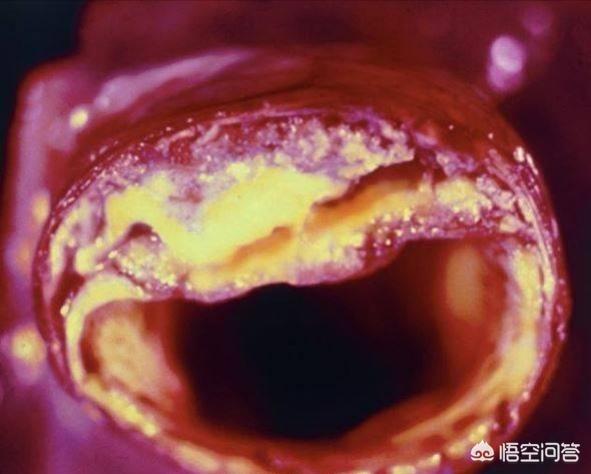

血管狭窄を引き起こし、最も深刻なプラークは、心血管プラーク、または頸動脈プラークであり、これらのプラークの悪化は、心筋虚血、脳虚血につながる;積極的に制御しない場合、あるいはプラークの血栓症の破裂が発生し、心筋梗塞、脳梗塞をもたらす。

高脂血症などの心血管危険因子の影響により、血管の内壁は徐々に傷つき、血液中の余分な脂質は徐々に血管壁の下に沈着し、黄色い粥腫性脂質コアを形成し、最終的には脂質コアに線維性被膜が形成され、これが動脈プラークの形成過程である。 プラークは動脈硬化を引き起こす危険因子であり、安定性や破裂に問題のあるプラークは、反応性血小板血小板の反応性凝集は血栓を形成し、動脈血管を閉塞させ、梗塞性心血管病を引き起こすことさえある。したがって、私たちはプラークの問題に注意を払う必要がありますが、通常、すでに形成されたプラークを元に戻したり除去したりすることは非常に困難であり、私たちがしなければならないことは、合理的な薬物療法と運動によってプラークの形成を予防し、既存のプラークに対して、プラークの安定性を維持するように努め、動脈硬化のプロセスを遅らせ、プラークの破裂がより大きなリスクを引き起こすのを防ぐことです。

プラークは、静脈プラーク、動脈プラークを持って、それは複数の病因因子の役割にある、沈殿物の脂質化のために、単刀直入に言えば、つまり、あなたがより多くのグリース、消化と使用することはできません、血中脂質4と他の多因子の影響下で、内膜に損傷を与え、血管の内層に沈着し、黄色のアテローム性脂質のコアの形成、および最終的に線維性キャップが持続的な炎症にさらされている場合、通常は非常に安定している脂質のコア、上の線維性コアの形成にある攻撃は、飲酒、怒り、夜更かし、少ない水を飲むなど、線維性キャップが破裂し、プラークが流出し、血液中の血小板が結婚フラッシュ、血栓と呼ばれるトラブルメーカーの子供を出産し、この子は、血管をブロックするために悪いことをすることに特化し、トラブルを作るためにさまよう、血管の内腔に血栓が同時に狭くなるだけでなく、破裂、急性心脳血管イベント、脳卒中、心筋梗塞、肺塞栓症、腎不全、静脈瘤などを誘発する。などである。したがって、プラークを除去することは、血管の詰まりを取り除くだけでなく、急性心血管系および脳血管系イベントを予防することにもなり、誰もが関心を寄せている。

動脈プラークは、複数の病因因子の影響下にある動脈内膜の損傷によって引き起こされる一連の炎症反応であり、後に二次的なアテローム性プラークが生成される。プラークの形成は人体にとってより有害であり、同時に血管の内腔を狭くし、破裂して急性心血管系イベントを誘発することもある。したがって、プラークを除去することは血管の詰まりを解消するだけでなく、急性心血管系イベントを予防することにもなり、これはすべての患者の心臓の鼓動である。プラークの治療には、血中脂質、血圧、血糖値などのコントロール、減塩、低コレステロール食、運動量の増加、禁煙、アルコール制限などの悪い生活習慣の改善など、病気の原因から始めるか、上記の治療の上に薬物療法を行うことができます。薬の選択は、アトルバスタチン、レセルプルバスタチンなどのスタチン系薬剤がアテローム性プラークの治療によく使用されます。具体的な治療計画は専門医の指導のもとに立てるべきである。

プラークが発生する過程にはいくつかの段階があり、まず血管の内皮が傷つき、血管内面の保護層が「壊れる」ようになると、血液中の高分子脂肪が低比重リポ蛋白と呼ばれる一種の物質によって血管壁の内膜中膜層に大量に運ばれて蓄積し、血管壁が肥厚し、医療では内膜中膜層が1mm以上になると動脈硬化が起こっていると言われています。内膜中膜層の肥厚が1mmを超えると、局所的に凝集して塊になったような動脈硬化、すなわち初期プラークが生じたといわれる。

初期のプラーク形成は、脂肪の蓄積が一連の炎症反応を引き起こし、実際には、脂肪は常に酸化変性、粥状物質の形成であり、これらの物質は、血管の正常な構造を破壊し、血管の一部となり、この時点で、脂質化された材料は、通常、ソフトスポットと呼ばれる液体の状態にほとんどである。

ソフトスポットの脂質化した物質は、皮膚感染症が膿を出すと線維化し痂皮化するように、時間の経過とともに壊死することがある。また、カルシウムが沈着すると石灰化が起こり、プラークが硬くなり、血管収縮機能がより低下する。このようなプラークはハードスポットと呼ばれる。